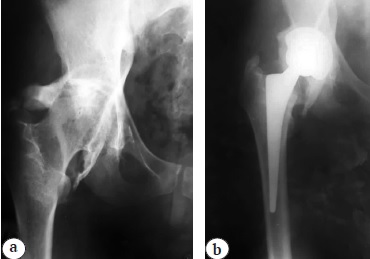

After ruling out the infectious process, the patient underwent re-endoprosthetics. During the access, the femoral abduction apparatus was moderately thinned, with signs of partial cicatricial degeneration of the musculus gluteus medius, but without significant defects. A combination of transgluteal and posterior approaches was used to resect the heterotopic ossificates. When performing a transgluteal approach, a bone bed was exposed around the endoprosthesis head located at the anterior–superior edge of the acetabulum. The bone bed was opened to mobilize the endoprosthesis head (Fig. 3 a,b). Then, through the posterior approach, the ossificates protruding above the posterior edge of the acetabulum and in the area of the sciatic nerve were visualized (Fig. 3c).

Fig. 3. Stages of the surgery: a — dissection of ossifications around the head of the endoprosthesis; b — removal of ossifications around the dislocated head of the endoprosthesis; c — visualization of ossifications

The sciatic nerve was also ossified. Resection of the ossificates around the nerve, extended release of the proximal femur, and resection of heterotopic ossificates capable of causing bone-to-bone or component-to-bone impingement were performed.